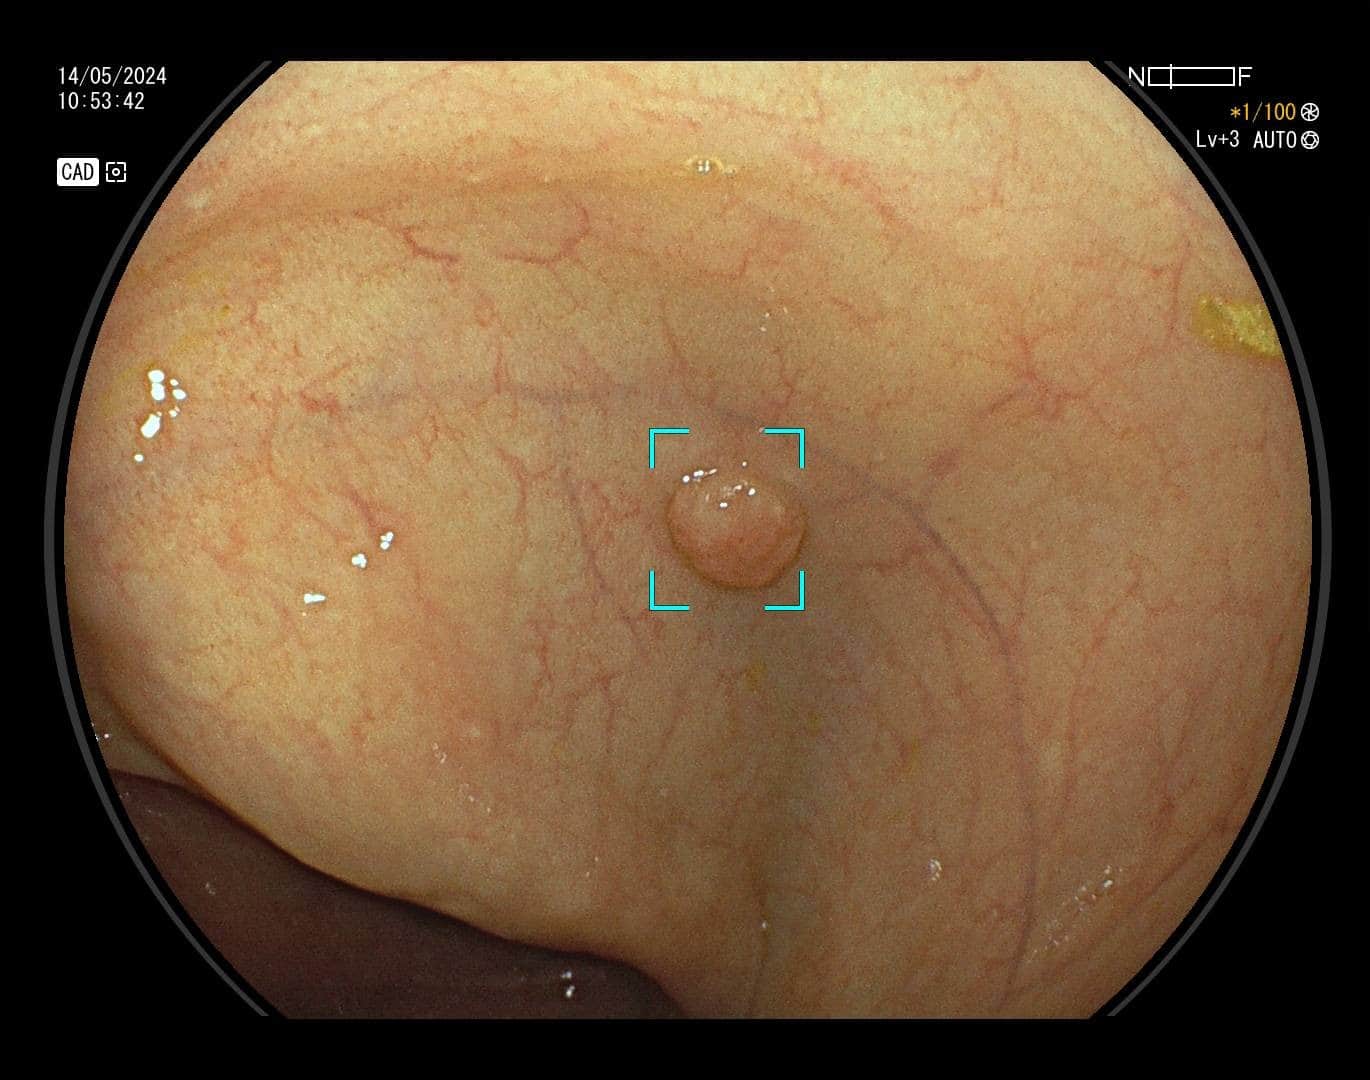

Karcinom debelog crijeva, prema podacima Hrvatskog registra za rak, drugi je po učestalosti uzrok maligne bolesti u žena, a treći u muškaraca. Ova vrsta raka razvija se iz polipa, malih izraslina na sluznici debelog crijeva koje nastaju pod utjecajem okolišnih i/ili genetskih čimbenika. S vremenom polip raste, stanice nakupljaju mutacije, te u konačnici dolazi do razvoja karcinoma. Na sreću, nemaju svi polipi zloćudni potencijal. Kod polipa visokog rizika proces do maligne transformacije je najčešće dugotrajan što nam daje priliku za preventivnim djelovanjem – preventivnu kolonoskopiju preporučuje se učiniti s navršenih 50 godina života, a u slučaju obiteljske sklonosti i u ranijoj životnoj dobi. Cilj pretrage nije dijagnosticirati karcinom već pravovremeno detektirati i ukloniti njegov predstadij – polip.

Kako bi pregled debelog crijeva bio temeljit potrebna je dobra priprema crijeva (očišćenost), no mali i plitki polipi, unatoč optimalnim uvjetima pretrage mogu ostati nezamijećeni, a zbog anatomije crijeva i skriveni iza nabora.